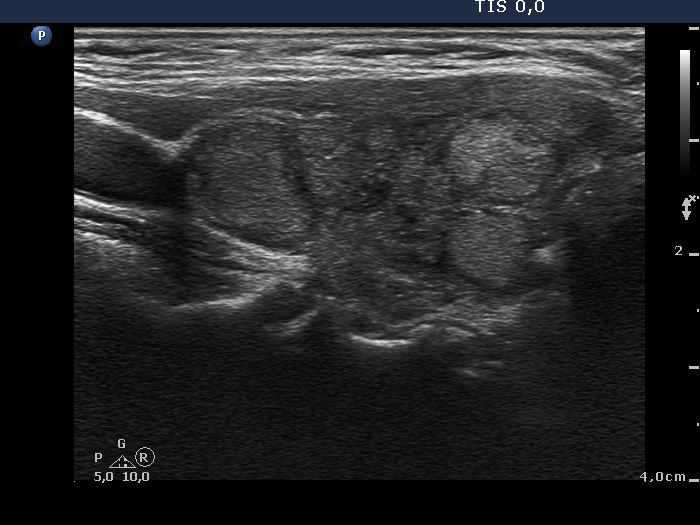

Study on 100 consecutive patients with thyroid nodule - case 025 (ultrasonographic picture 3)

Right lobe, longitudinal scan. The presence of multiple nodules with the maximal diameter ranging form 7 to 20 mm, makes the appearance of the lobe micronodular.